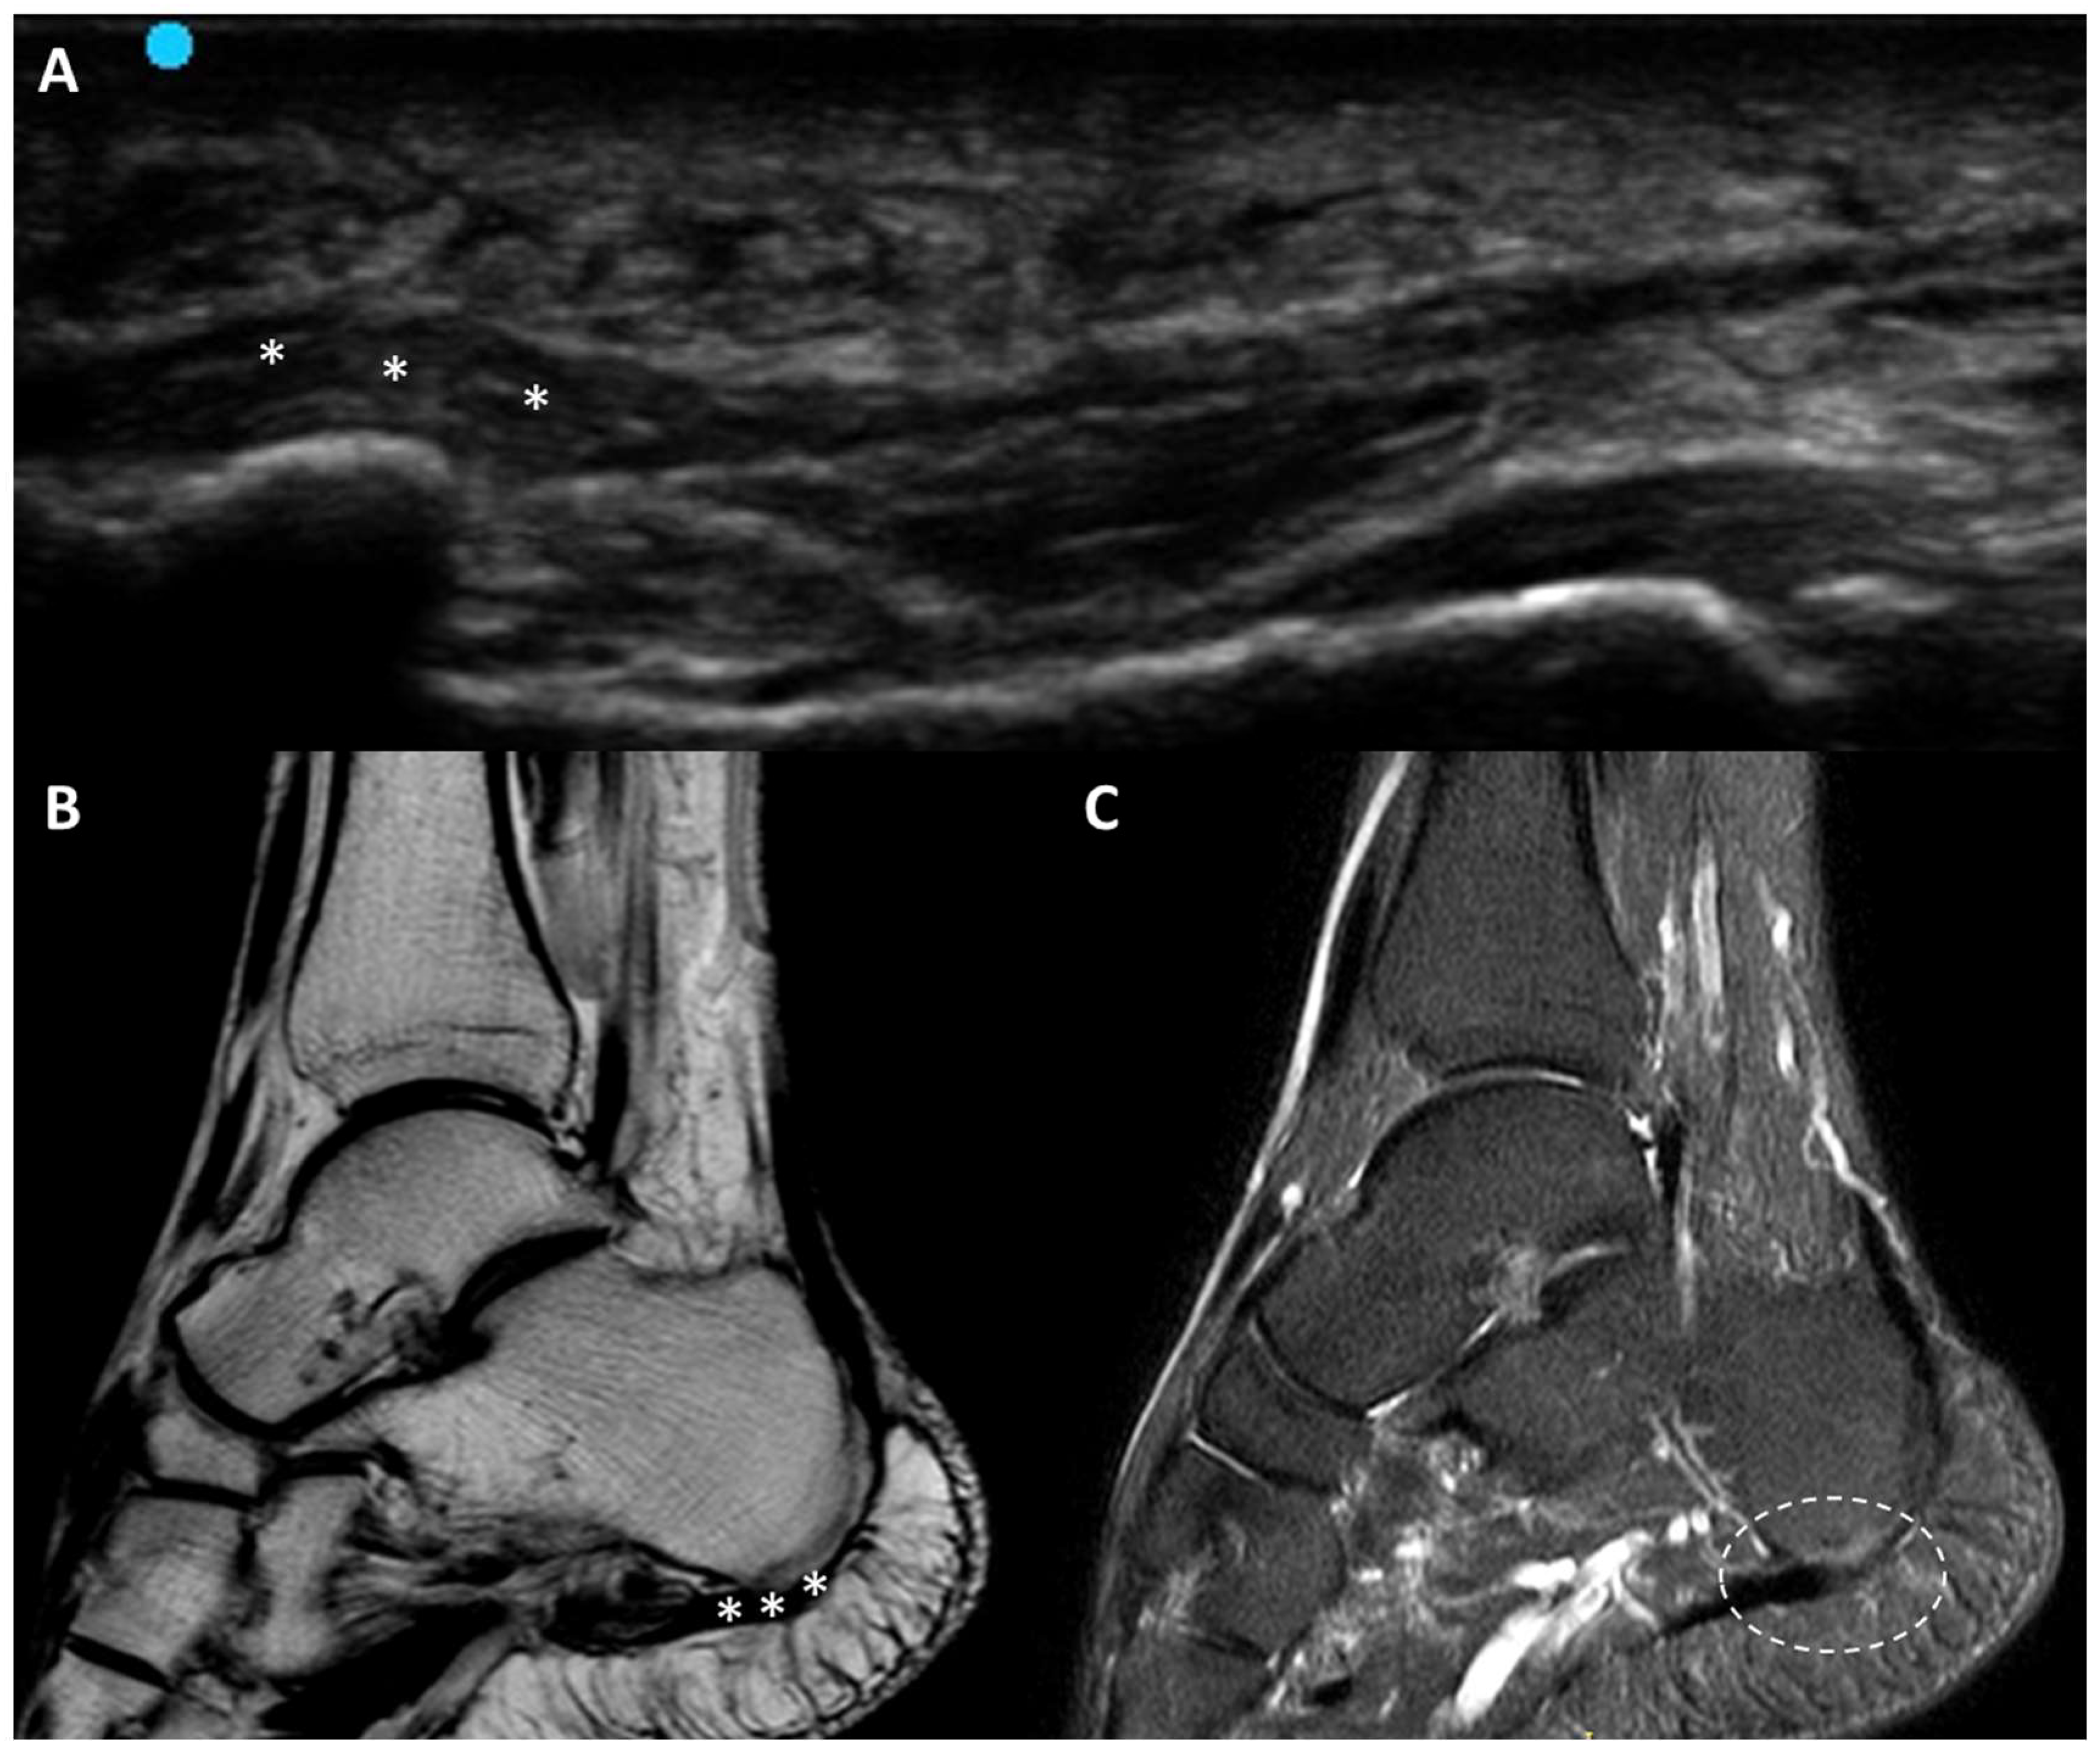

3.5.6. Plantar Fascial Rupture

- Louwers, M.J.; Sabb, B.; Pangilinan, P.H. Ultrasound evaluation of a spontaneous plantar fascia rupture. Am. J. Phys. Med. Rehabil. 2010, 89, 941–944. [Google Scholar] [CrossRef] [PubMed]

- Deka, J.B.; Deka, N.K.; Shah, M.V.; Bortolotto, C.; Draghi, F.; Jimenez, F. Isolated partial tear of extensor digitorum longus tendon with overlying muscle herniation in acute ankle sports injury: Role of high resolution musculoskeletal ultrasound. J. Ultrasound 2022, 25, 369–377. [Google Scholar] [CrossRef] [PubMed] [PubMed Central]